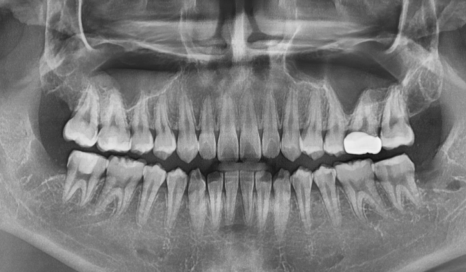

내원 당시 살펴보니

사랑니는 비스듬히 누워 반쯤만

잇몸 밖으로 나온 상태였습니다.

240919

엑스레이와 입안 사진을 통해 확인해 보니,

230227(전) 240919 (후)

1년 반 사이에 사랑니뿐만 아니라,

앞에 치아까지 충치가 생겨있었습니다.

심지어 충치가 꽤나 많이 진행되어

이미 신경 가까이까지 진행된 상황이었습니다.